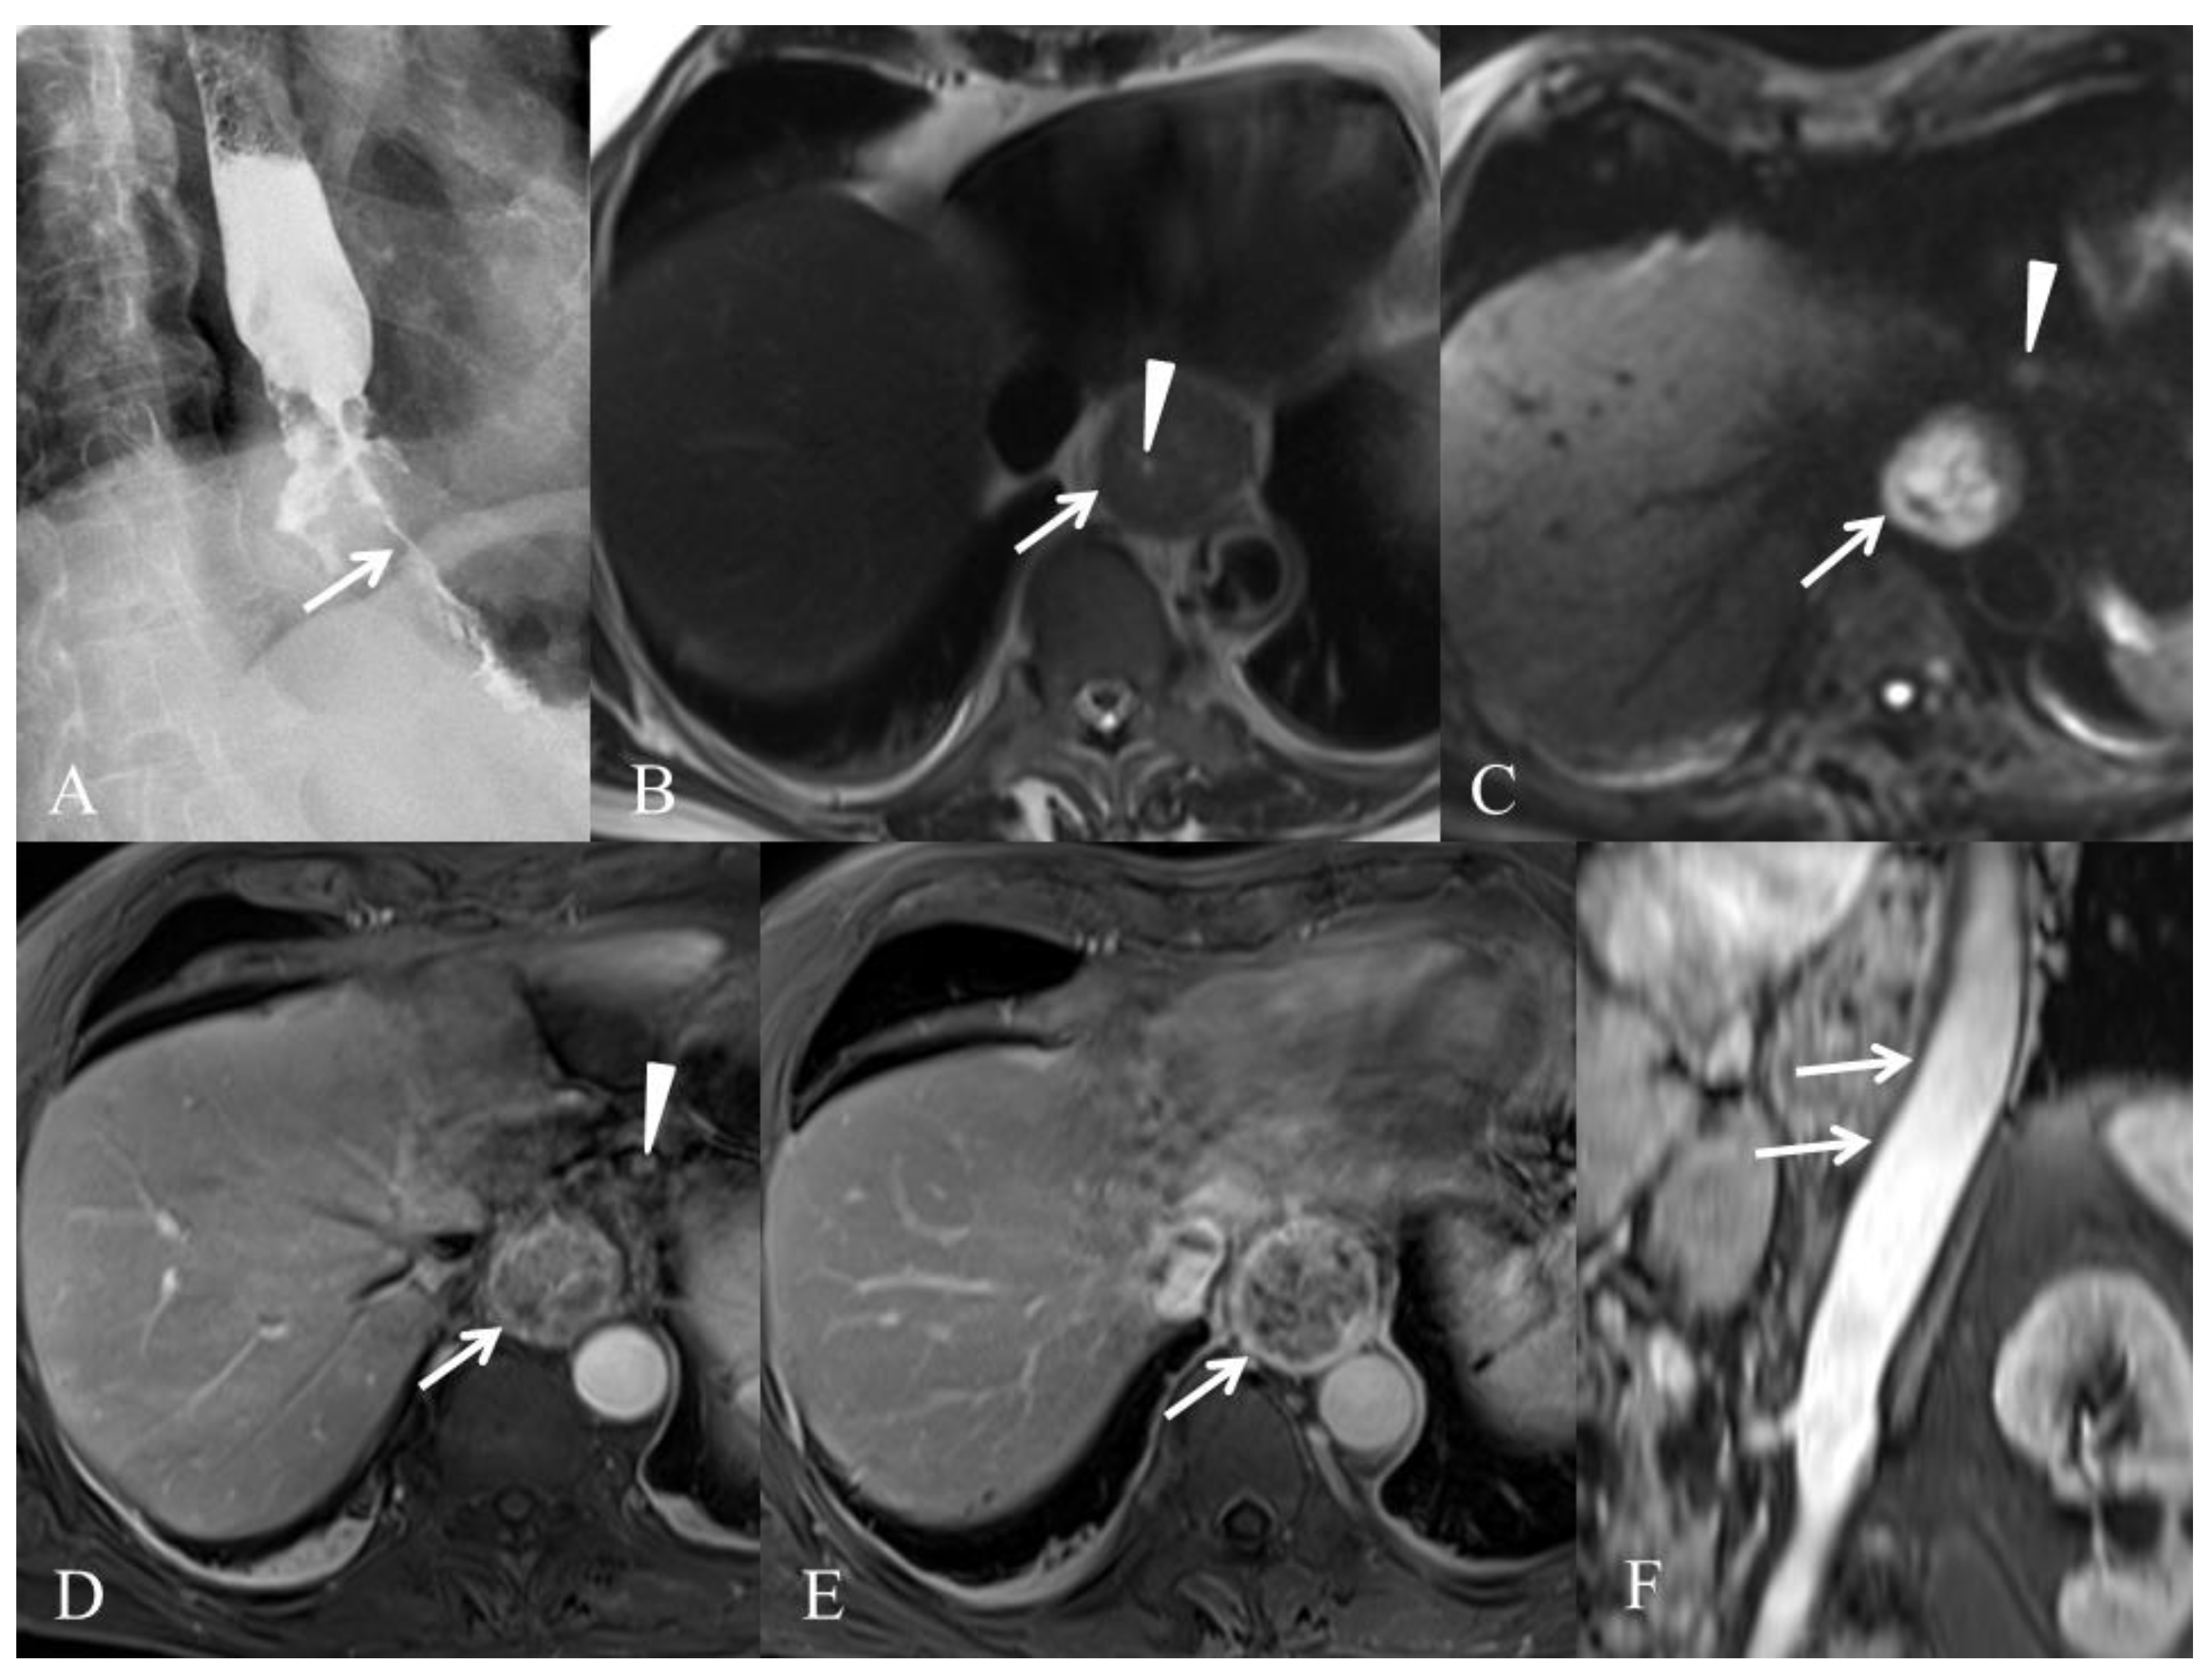

3.1. Initial Tumor (T) Staging

3.2. Node (N) Staging

3.4. Target Volume Delineation before Irradiation